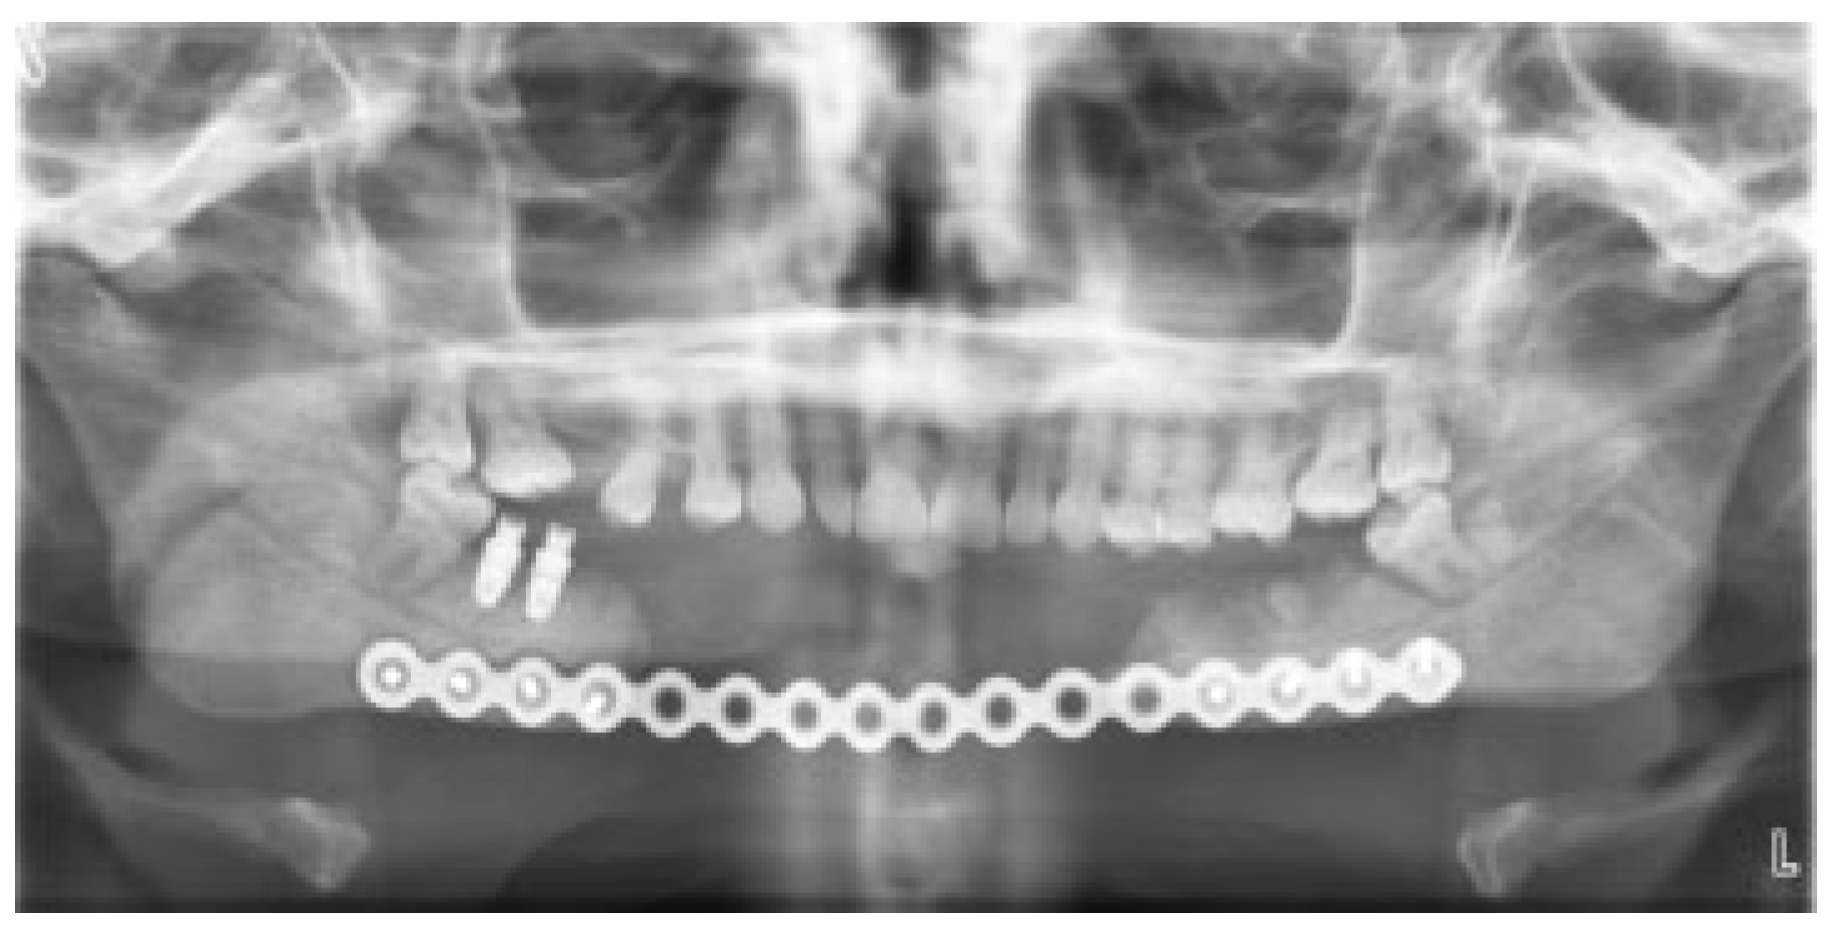

Plain film imaging demonstrated the mandibular reconstruction plate in place, with no findings suggestive of recurrent disease at the margins (Figure 2). The mandibular width and symmetry had been maintained by the reconstruction plate.

Figure 2. Panoramic radiograph demonstrating large mandibular defect involving the symphysis with a reconstruction plate in place. The patient is nearly edentulous in the mandible and has only single contacts on molars bilaterally.